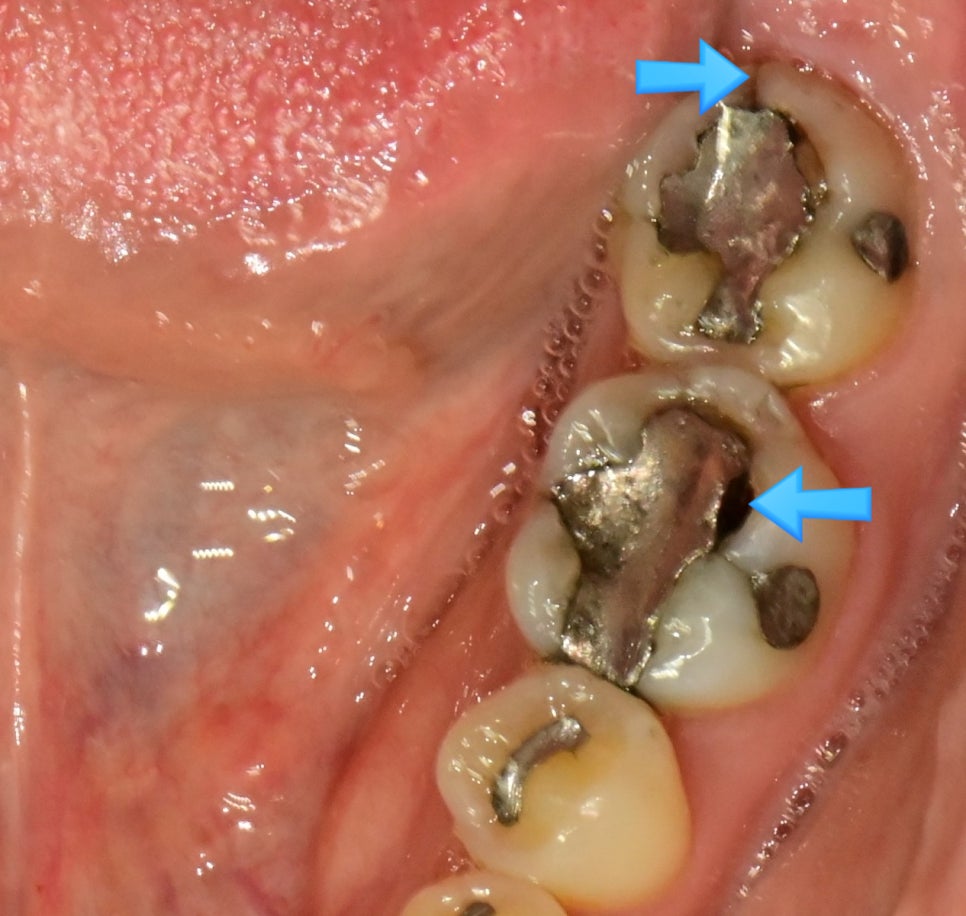

상악 교합면 사진 — 4개 치아에 아말감 충전물이 파란 화살표로 표시된 before 임상 사진

▲ 아말감으로 충치 치료를 여러 개 받으신 환자분의 상악 교합면